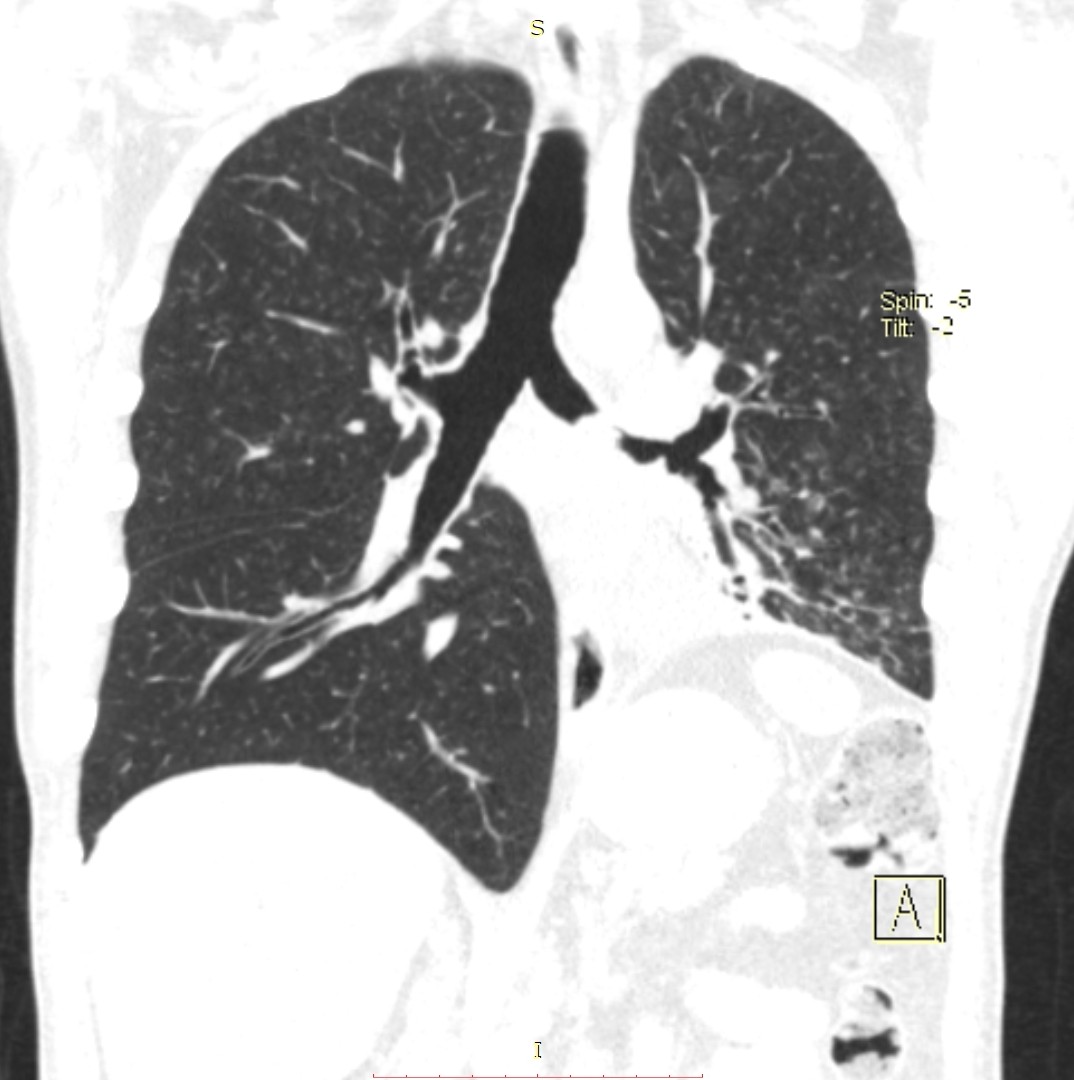

- გულმკერდის კტ (Coronal) სტენტირებამდე 5 დღით ადრე

აღინიშნება მარცხენა მთავარი ბრონქის ოკლუზია სიმსივნური წარმონაქმნით